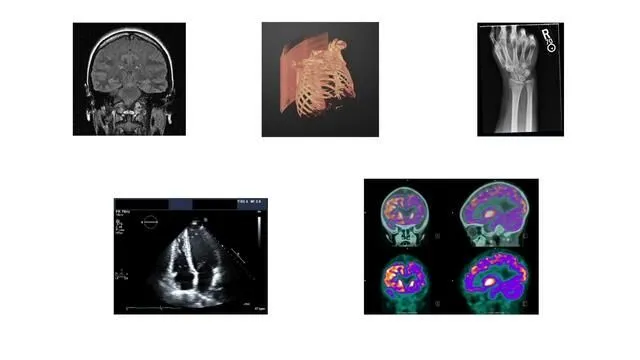

You can import, preprocess, and analyze radiology images from various imaging modalities, including projected X-ray imaging, computed tomography (CT), magnetic resonance imaging (MRI), ultrasound (US), and nuclear medicine (PET, SPECT). The Medical Image Labeler app lets you semi-automate 2D and 3D labeling for use in AI workflows. You can perform multimodal registration of medical images, including 2D images, 3D surfaces, and 3D volumes. The toolbox provides an integrated environment for end-to-end computer-aided diagnosis and medical image analysis.